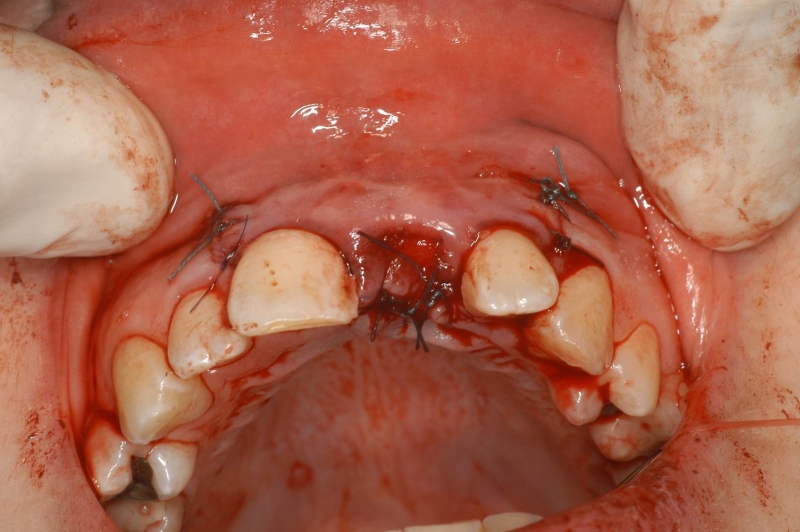

08/12 - Wound closure

Treatment of dehiscence defect with cerabone® & Jason® membrane - Dr. M. Steigmann

09/12 - Wound closure, occlusal view